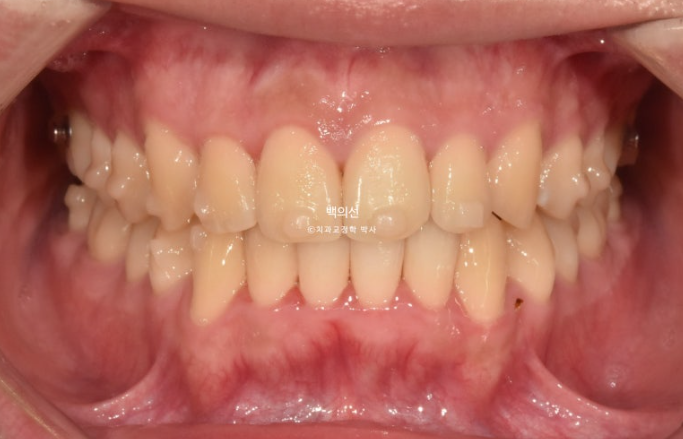

25.07

어금니 교합이 약간 뜨는 부분들이 있습니다.

앞니 배열은 좋아졌습니다.